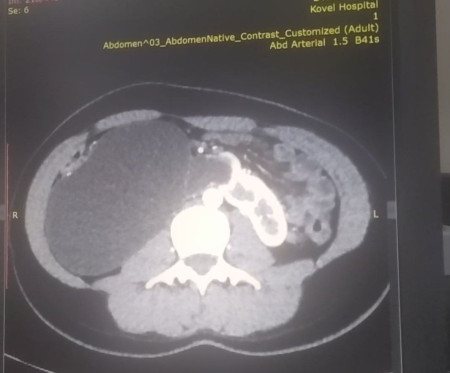

Вперше у Ковелі провели унікальну урологічну операцію 17-річній пацієнтці, яка мала вроджену ваду сечовидільної системи – підковоподібну нирку (зрощення двох нирок). Стан її здоров’я погіршувався упродовж багатьох років, аж поки права половина підковоподібної нирки перестала функціонувати.

Хвору доставили в лікарню у важкому стані з вираженим больовим синдромом та наявністю гіпертонічного кризу. Через звуження у сечоводі та ускладнення відтоку сечі, об’єм рідини в нирці сягнув критичного рівня. А збільшення її розмірів стало помітним навіть зовні.

Лікарі діагностували термінальний гідронефроз із наслідками, гідронефротичну трансформацію правої половини підковоподібної нирки, вторинну артеріальну гіпертензію.